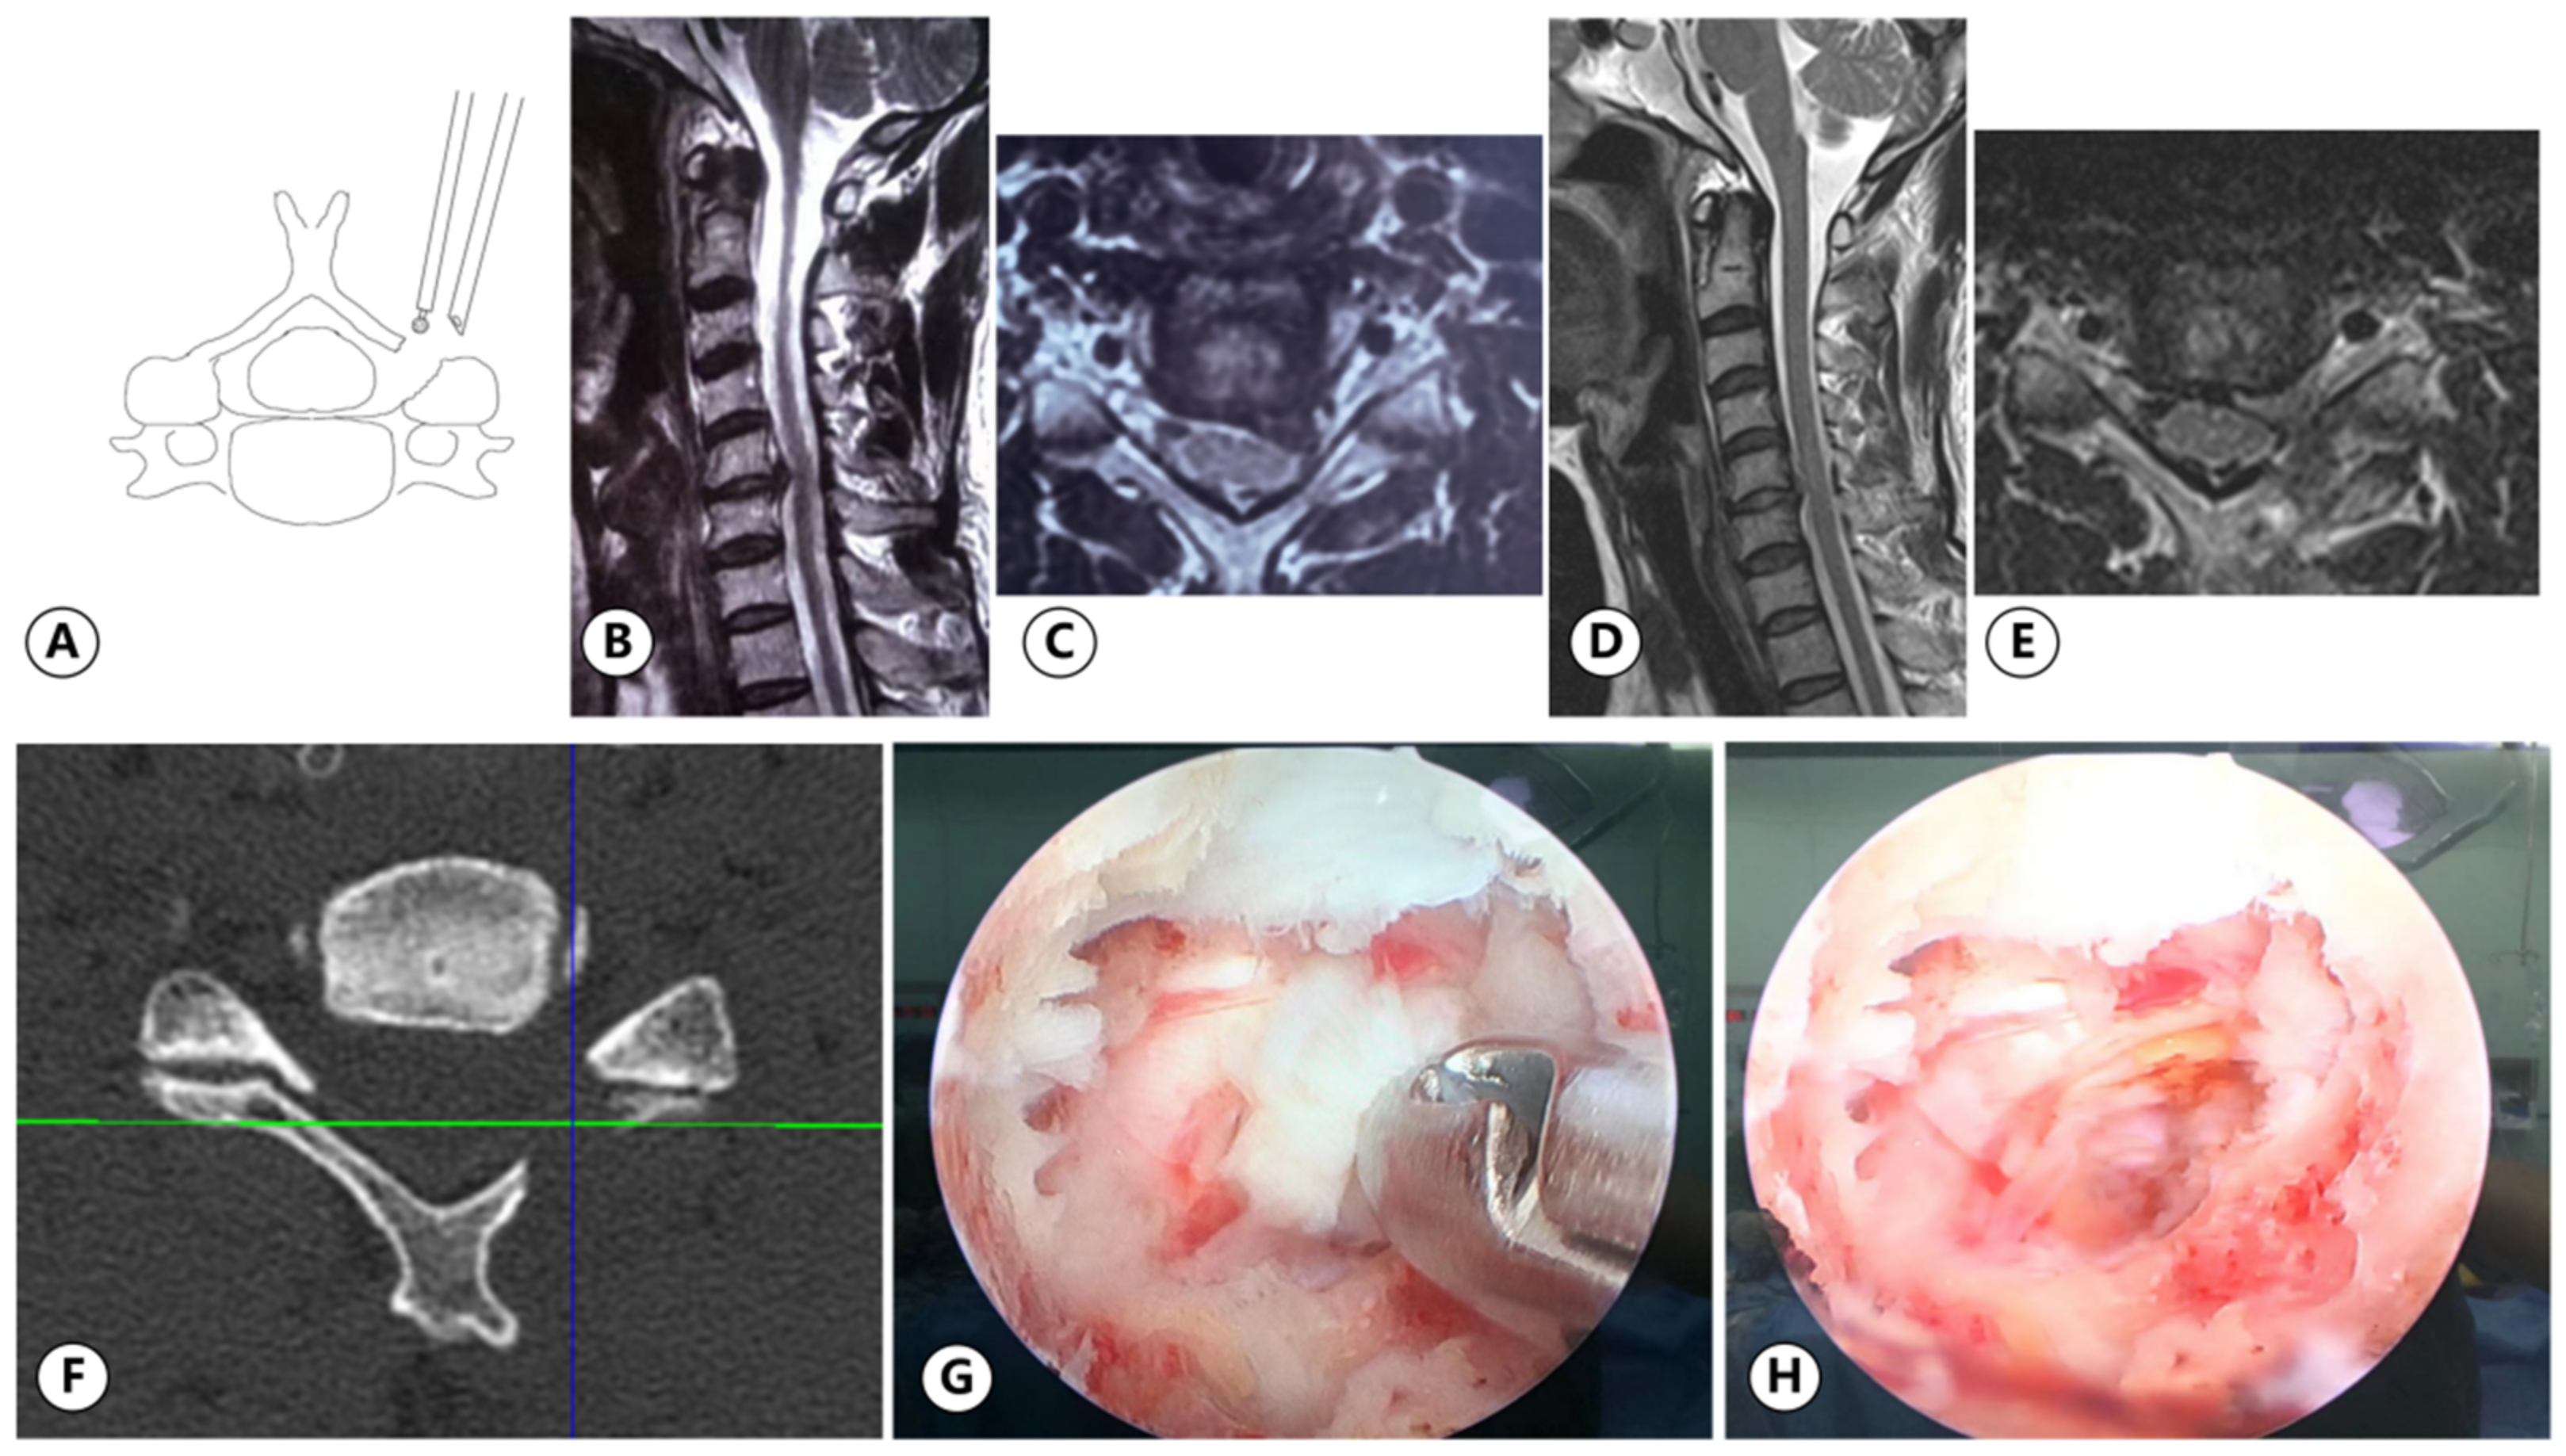

2.3.1. UBE

2.3.2. PE